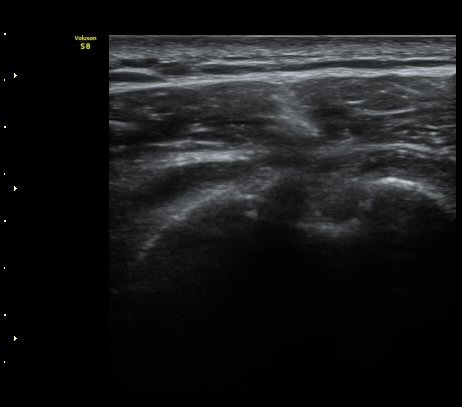

±Ø»ó°Ç³»Ãø Á¾´Ü¸é°Ë»ç¿¡¼­ ±Ø»ê°Ç ºÎÂøºÎÀÇ  ÀÛÀº ÆÄ¿­°ú Á¡¾×³¶ ºÎÁ¾ÀÌ °üÂûµÊ(±×¸² 2, 3).